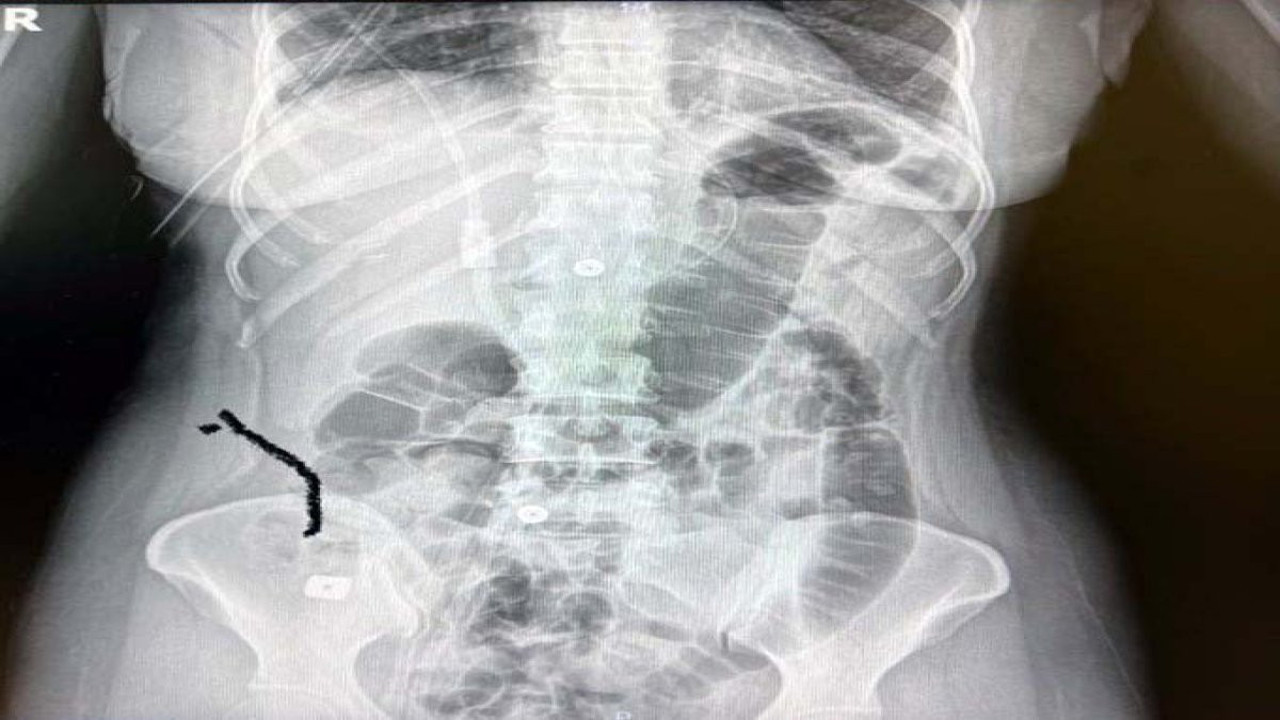

Doktorunun tavsiyesi ile boynuna implant yerleştirildi. Bir süre sonra ağrıları devam eden Tıraş, Gaziantep'te özel bir hastaneye başvurdu. Burada yapılan kontrollerde boynuna takılan implantın yerinden oynadığı tespit edildiği için ameliyata alındı. Ameliyat sırasında implantlardan birisi çıkarılırken, diğeri tespit edilemeyince doktorunun tavsiyesi ile kentteki özel bir üniversitenin hastanesine sevk edildi. Burada endoskopi yapılan Sultan Tıraş'ın yemek borusunda yırtık olduğu, implantın da midesinde bulunduğu tespit edildi. Yoğun bakım ünitesine alınan Sultan Tıraş, yapılan hazırlıkların ardından Prof. Dr. Levent Elbeyli tarafından ameliyata alındı. Tıraş, riskli olarak değerlendirilen ameliyatının başarılı geçmesiyle sağlığına kavuştu. Tıraş'ın sağlık durumu ile ilgili düzenlenen basın toplantısına ameliyatını gerçekleştiren Prof. Dr. Levent Elbeyli, SANKO Üniversitesi Tıp Fakültesi Dekanı Prof. Dr. Salih Murat Akkın, Doç. Dr. Nimet Yılmaz ve Doç. Dr. Betül Şimşek katıldı.

Yaşanan bu olayın tıp literatüründe görülmediğini belirten Elbeyli, yapılan radyolojik tetkikler ve değerlendirmeler sonucu daha önce başka bir merkezde boyun omurlarına yerleştirilen metal disklerin yerinden oynadığını ve birisinin de midede olduğunun tespit edildiğini kaydetti.

“Sultan Hanım bize bir başka hastaneden, bir beyin cerrahi uzmanımızın bir referansı ile gönderildi. 1 yıl önce Gaziantep dışında bir şehirde hastanede boyun fıtığı ameliyatı geçiriyor. Burada bir takım plak ve tıbbı anlamda enstrümanlar kullanılır. Bu hastamıza da iki adet implant takılmış ve zaman içinde yerinden oynayarak yemek ve nefes borusunda bir sıkıntı yarattığını hastamızdan öğrendik. Daha sora çekilen MR ve radyolojik tetkiklerle belirleniyor. Semptomların iyice artması karşısında hastamız bize yönlendiriliyor. Yaptığımız incelemelerde bu implantların yerinden oynadığı ve bir şekilde yer değiştirdiğini gördük. Bu alan komplike bir alan. Yapılan endoskopide yemek borusunda bir delinme olduğunu tespit ettik. Devamında midede bu implantların birinin görünmesi söz konusu. Diğer implantın da yerinden oynadığını görüyoruz. Böyle bir durumda hayati tehlikesi son derece yüksek. Yemek borusu kontamine bir alan. Hastayı direkt yoğun bakıma aldık. Bu kritik tablonun tedavi sürecini başlattık. Hayati tehlikenin yüksek olduğunu da hasta yakınları ile görüşüp bilgilendirdik. Ameliyatla yemek borusuna kaçan ve hatta nefes borusunda da tahrip olmuş olabileceği bilgisini ve birkaç aşamada cerrahi işlem gerektiğini belirttik. Ameliyat göğüs boşluğu ve boyun bölgesinden delinmenin olduğu yerin ameliyatla görülmesi ve tedavinin yapılmasıydı. 6 saati geçen bir ameliyat sürecimiz oldu. Hastanın boyun kısmından yaklaşık yarım litre iltihabi ve prülan ve gıda artıkları olan cerahat atığı temizlendi. Uzun süre kaçak nokta temizlendi ve tedavi edildi. Orada iğne ucu kadar bile açık bırakma şansınız yoktur. Ameliyatı başarıyla tamamladık. 3 gün yoğun bakımdan sonra sağlığına kavuştu. Ameliyattan sonra daha birtakım risklerin olabileceğini anlattık. Yoğun bakımın ardından hastamıza 10 gün kadar da serviste tedavi uyguladık. Bunun ardından hastamızı normal beslenir ve hayatını normal şekline koyarak evine yolcu ettik. Bugün çok sağlıklı ve aramızda.”